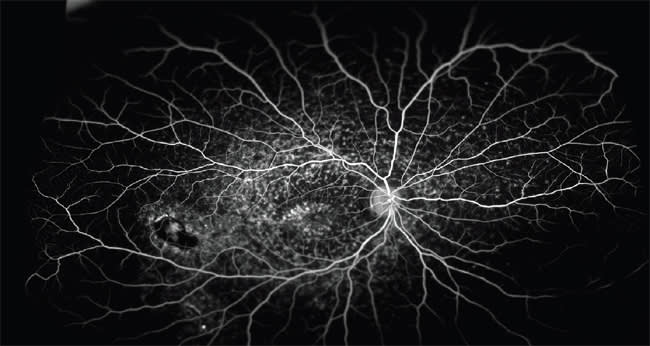

Figure 2. Superotemporal BRVO with secondary macular and peripheral ischemia. Note compensatory collateral formation.